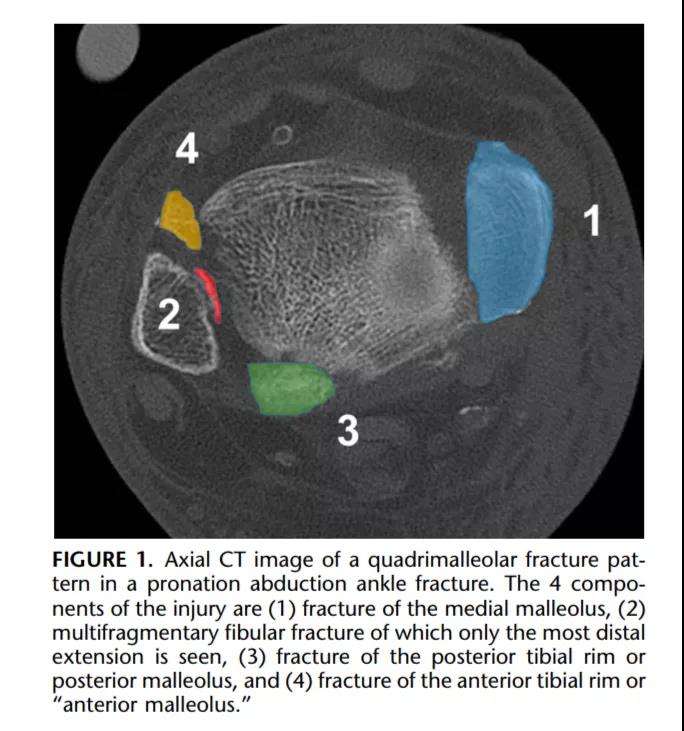

① 四踝骨折示意图:1.内踝;2.外踝;3.后踝;4.胫骨前结节(前踝)。

⑧ 复位后典型病例图。